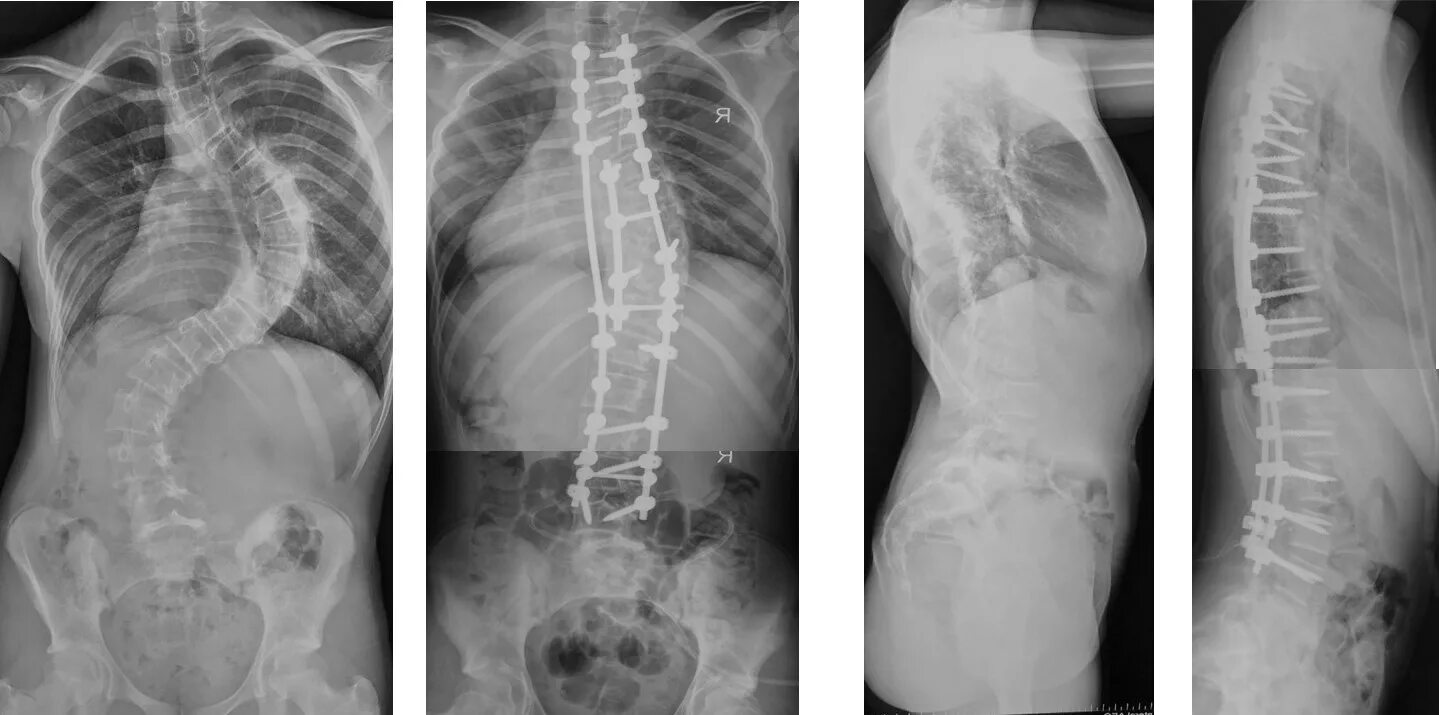

Кифосколиоз мкб